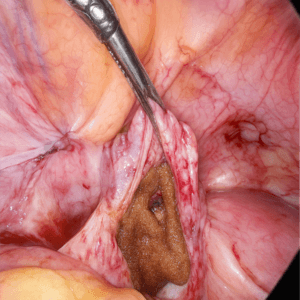

ORC placed in cystectomy bed to control Post cystectomy oozing

At the application site for Haemostasis during Right Salpingotomy